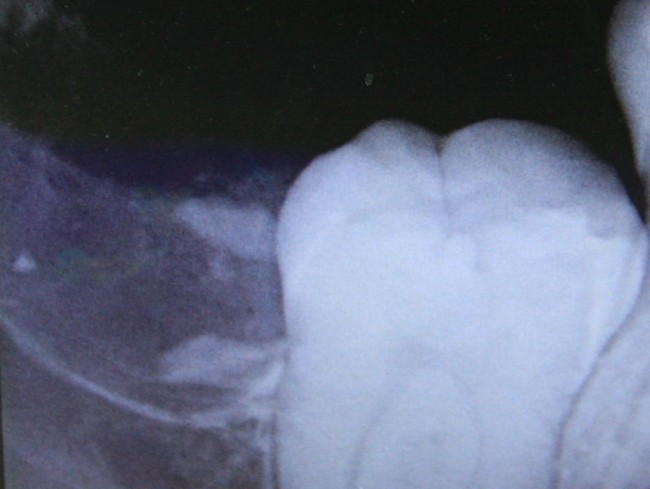

Однажды ко мне обратилась девочка по направлению от ортодонта. Принесла снимок:

Помимо аномального положения зуба мудрости есть еще одна проблема: восьмерка заблокировала седьмой зуб, в результате он не может прорезаться. В другой клинике ей предложили удалить два зуба, но она, по совету своего доктора, решила обратиться к нам в клинику.